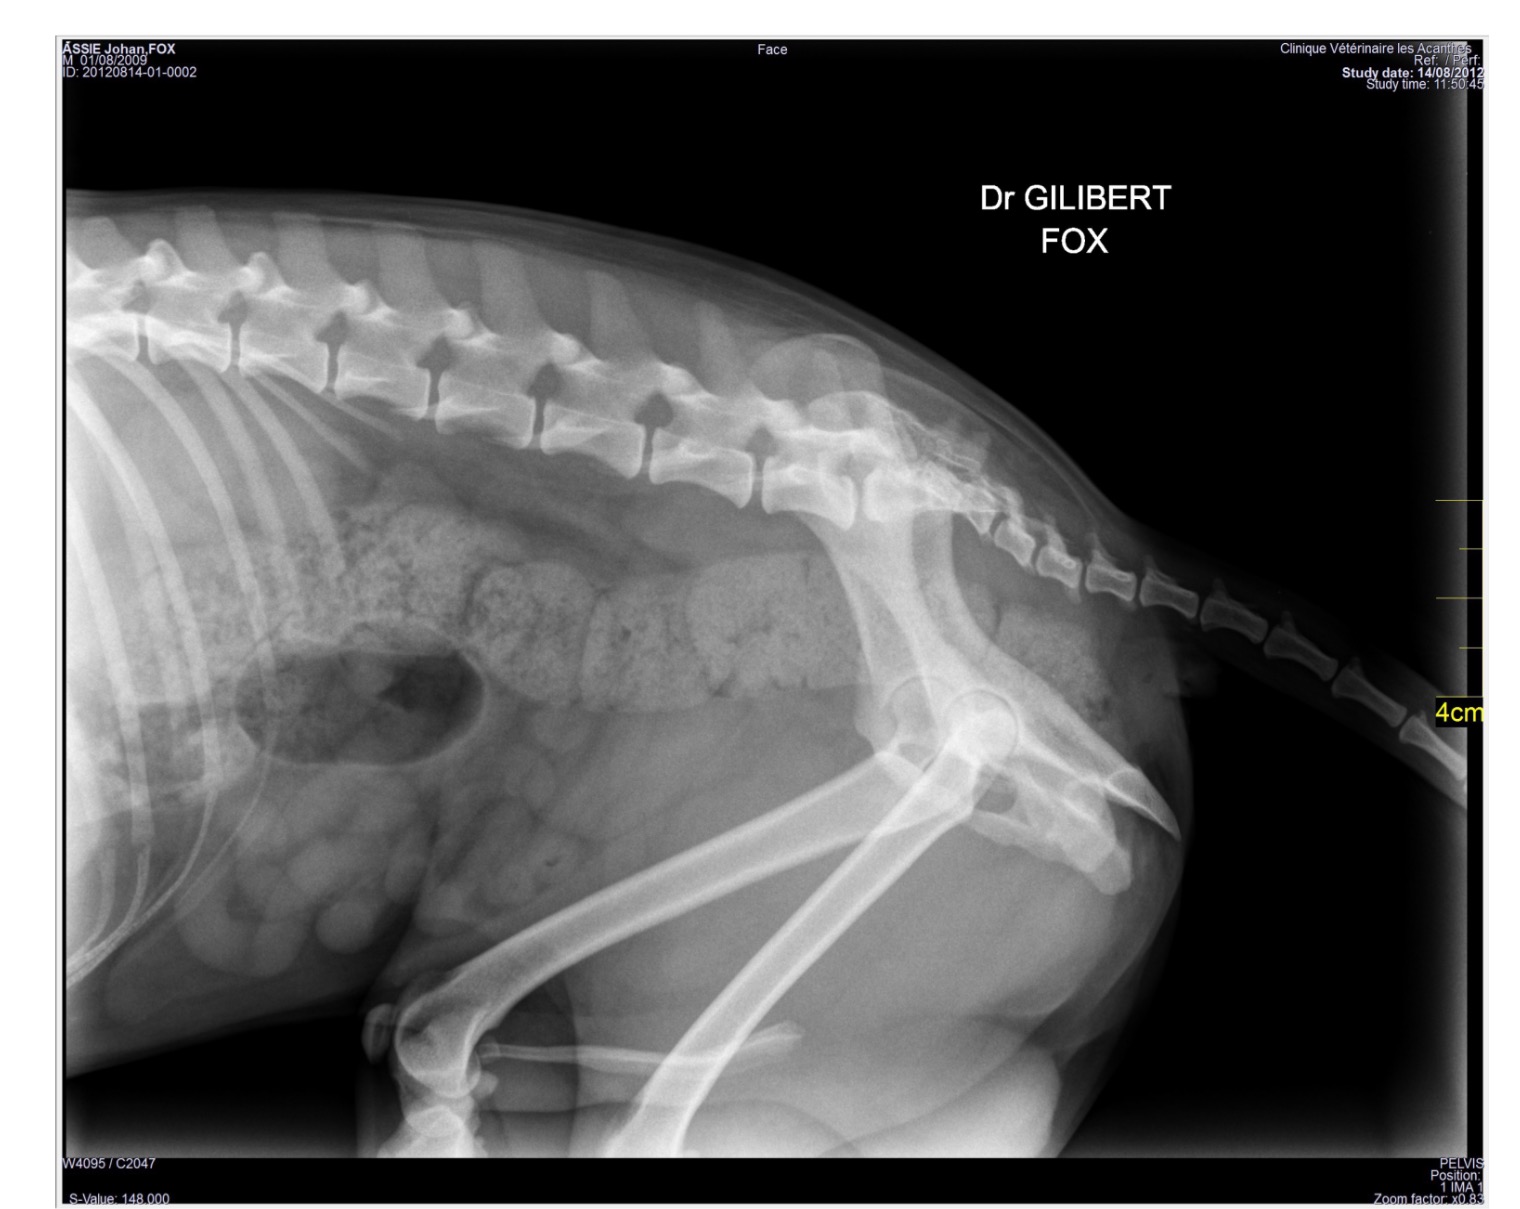

Fox est présenté à la consultation d’ostéopathie le 14/09/2012 en raison d’une intense douleur de l’arrière train entraînant une démarche sur les antérieurs uniquement. Fox a été, un mois auparavant, victime d’un accident de la voie publique. Il présentait alors une ataxie postérieure avec déficit moteur bilatéral. Des radiographies du bassin ont mis en évidence des fractures multiples : ischium, symphyse pubienne avec déplacement craniolatéral, esquille osseuse dans le foramen obturé droit et fissure du sacrum. Du tramadol (Contramal ND) à la dose de 1 mg/kg deux fois par jour et des antiinflammatoires non-stéroïdiens (0,5 mg par jour per os de Metacam ND) sont prescrits pour quinze jours avec une mise au repos en cage pour trois semaines, les propriétaires ne souhaitant pas d’intervention chirurgicale. Après un mois d’immobilisation, la douleur est très vive et l’état de Fox dégradé. Les propriétaires envisagent l’euthanasie. Illustration 1 : Vue de profil du bassin

Illustration 1 : Vue de profil du bassin Illustration 2 : Vue de face du bassin

Illustration 2 : Vue de face du bassin